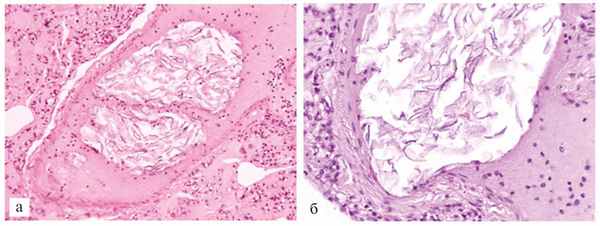

Гистологически в артериях, артериолах и капиллярах легких на фоне выраженного внутриальвеолярного отека, очаговых внутриальвеолярных кровоизлияний и десквамации альвеолоцитов выявили многочисленные эмболы и тромбы, включающие элементы ОВ (роговые чешуйки, жир, слизь, редко волосы). В зависимости от составных частей эмболов представляется возможным разделить их на следующие виды: 1) жировые массы и роговые чешуйки, 2) лейкоциты и роговые чешуйки, 3) лейкоциты, зернистые массы и единичные роговые чешуйки, 4) слизь, лейкоциты и роговые чешуйки (рис. 4). Рис. 4. Скопления частиц ОВ в центральной части артерии легкого. Ув. 200 (а); роговые чешуйки ОВ в артерии легкого. Ув. 600 (б). Окраска гематоксилином и эозином. В эмболах первого вида, если они находились в контакте с лейкоцитами, роговые чешуйки хорошо окрашивались гематоксилином после предварительной обработки срезов 0,5% раствором КОН, в остальных же видах эмболов они слабоэозинофильны, однако отчетливо выявлялись при окраске альциановым синим и при PAS-реакции.

Эмболы, состоящие из сыровидной смазки и эпителиальных чешуек, если они занимали весь просвет артерии, имели тенденцию располагаться в центральной части, окруженные эритроцитами. Эмболы с наличием слизи чаще располагались пристеночно или отделялись от эндотелия скоплениями лейкоцитов, роговых чешуек и зернистых масс. В эмболах (тромбах), содержащих зернистые массы, изредка выявляли фибрин. Эмболы из элементов ОВ также обнаруживали в сосудах миометрия по краю разрыва матки.